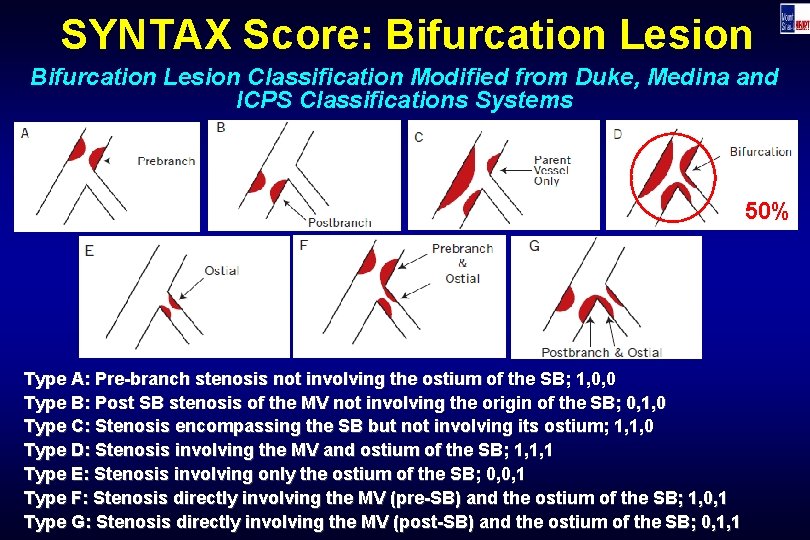

SYNTAX Score: Bifurcation Lesion Classification Modified from Duke, Medina and ICPS Classifications Systems 50% Type A: Pre-branch stenosis not involving the ostium of the SB; 1, 0, 0 Type B: Post SB stenosis of the MV not involving the origin of the SB; 0, 1, 0 Type C: Stenosis encompassing the SB but not involving its ostium; 1, 1, 0 Type D: Stenosis involving the MV and ostium of the SB; 1, 1, 1 Type E: Stenosis involving only the ostium of the SB; 0, 0, 1 Type F: Stenosis directly involving the MV (pre-SB) and the ostium of the SB; 1, 0, 1 Type G: Stenosis directly involving the MV (post-SB) and the ostium of the SB; 0, 1, 1